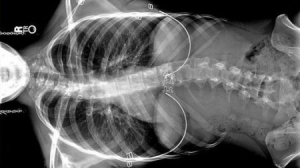

• 首台磁性控制骨骼矫正器

首台磁性控制骨骼矫正器

脊柱侧弯是一种后天性脊柱扭曲现象,常见于青少年儿童,会导致呼吸困难,走路歪斜等症状。传统疗法多通过手术,每隔六个月将植入的骨骼校正装置重新调整角度,“强迫”性将脊柱回归原位。近日,香港大学医学研究者创 ...……